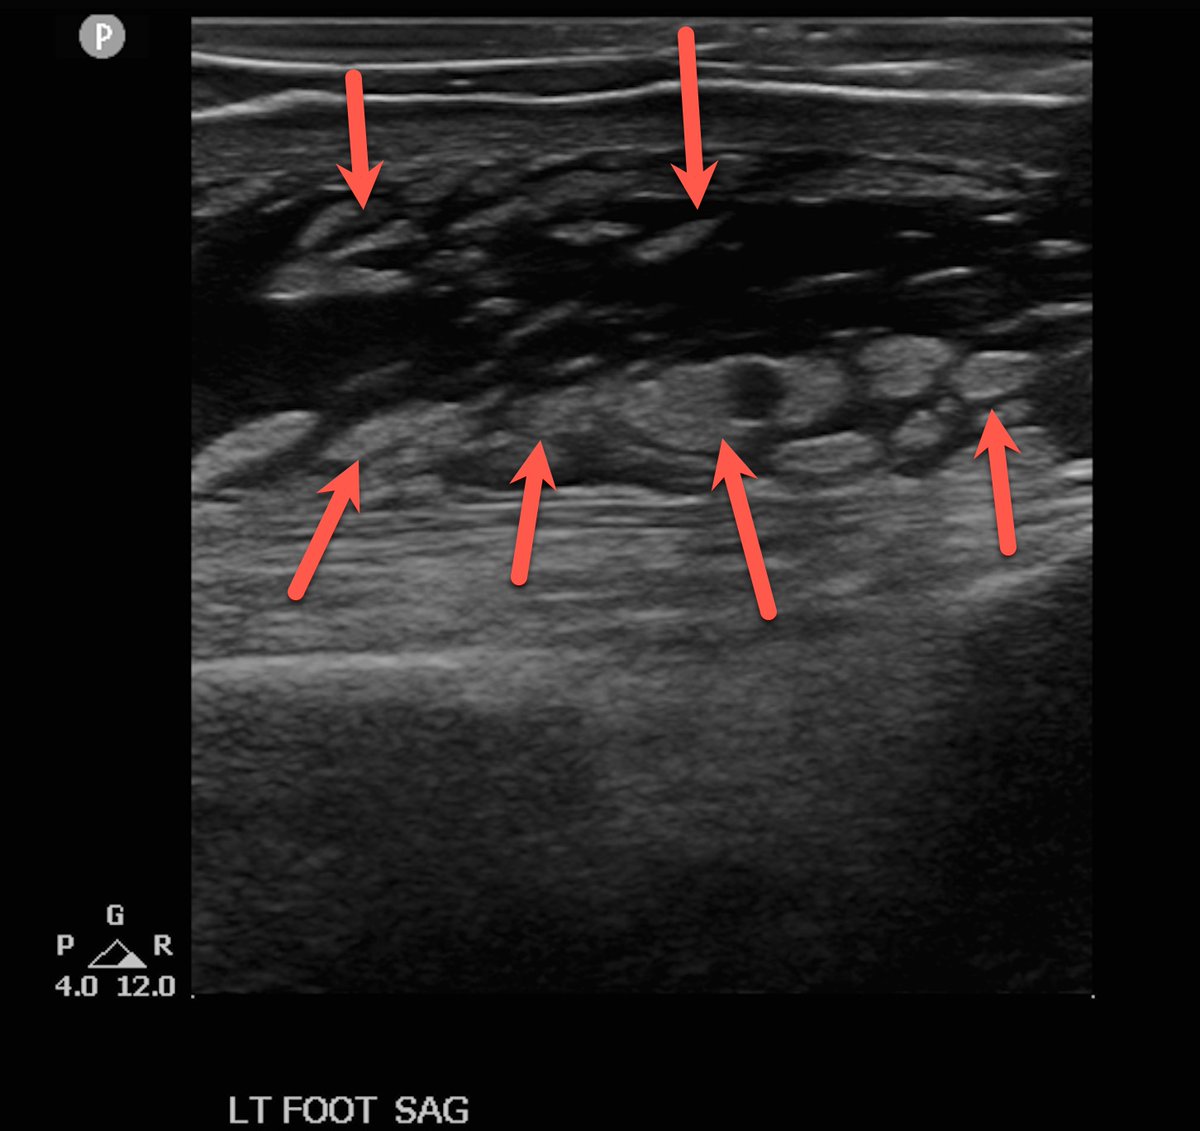

Came to India 🇮🇳 for family medical reasons. The beauty of being an Anesthesiologist 🇺🇸/ Anaesthetist 🇬🇧/ Anaesthesiologist 🇮🇳 and also being an expert in #RegionalAnesthesia #RegionalAnaesthesia & #POCUS! A small 🧵

❓ What does this clip show? Answer: Significant soft-tissue cobblestoning caused by edema (red arrows) in a patient who had just sustained multiple yellow-jacket stings to the foot. Cobblestoning can appear in cellulitis — but it isn’t pathognomonic. 🧠 Learning tip (PF